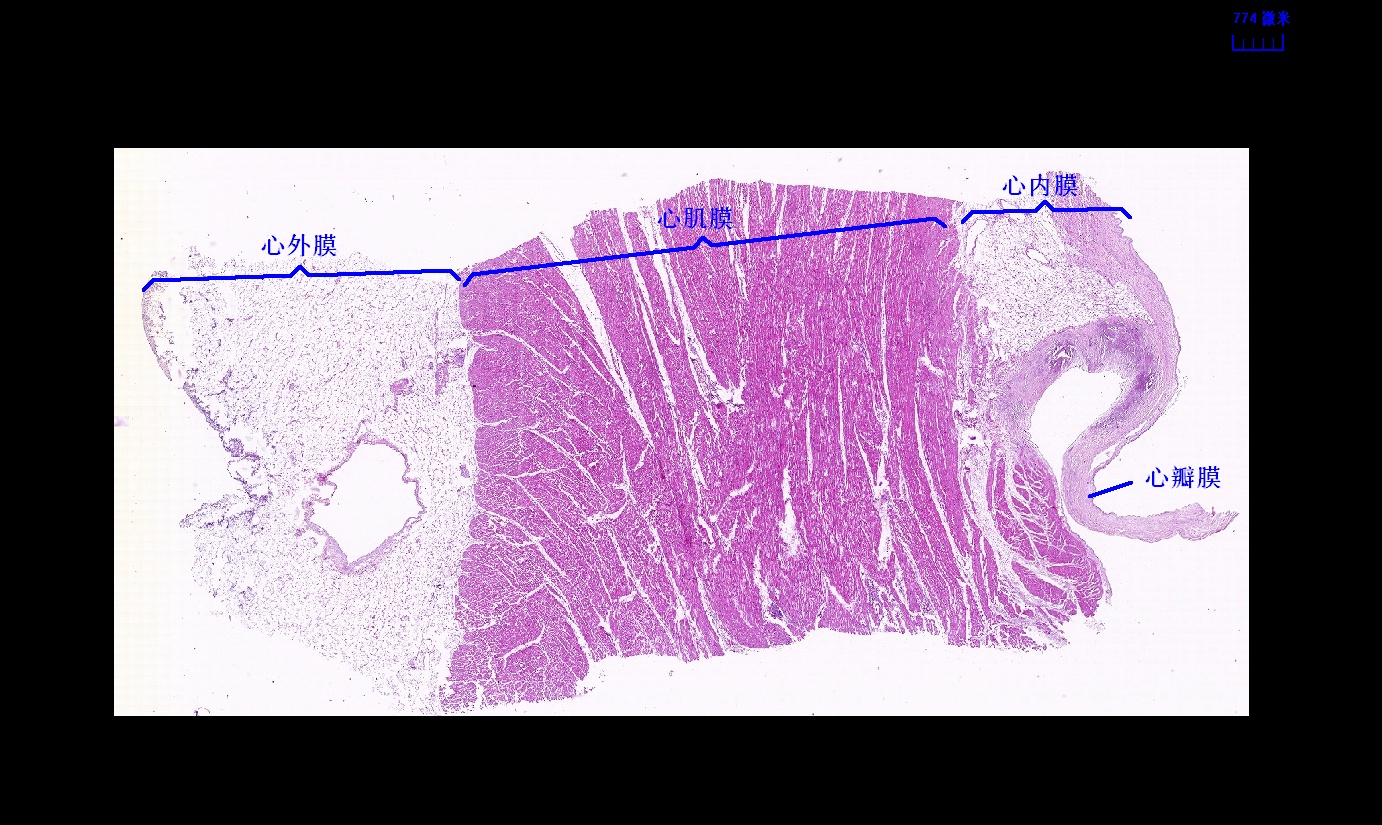

6.1 循环系统切片库

6.2 循环系统微课

6.3 循环系统课件